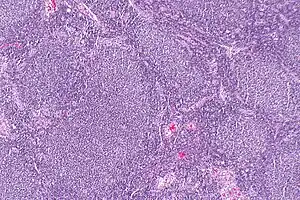

| Micrograph of a follicular lymphoma, showing the characteristically abnormal lymphoid follicles that gave the condition its name. H&E stain. | |

Follicular lymphoma (FL) is a cancer that involves certain types of white blood cells known as lymphocytes. The cancer originates from the uncontrolled division of specific types of B-cells known as centrocytes and centroblasts. These cells normally occupy the follicles (nodular swirls of various types of lymphocytes) in the germinal centers of lymphoid tissues such as lymph nodes. The cancerous cells in FL typically form follicular or follicle-like structures (see adjacent Figure) in the tissues they invade. These structures are usually the dominant histological feature of this cancer.[1]

The diagnosis of FL depends on examining involved tissues for histological, immunological, and chromosomal abnormalities that are indicative of the disease. FL usually involves enlarged lymph nodes populated by abnormal follicles (see adjacent picture) that when examined histologically contain a mixture of centrocytes or centroblast surrounded by non-malignant cells, mostly T-cells. The centrocytes, which typically outnumber centroblasts, are small to medium-sized B-cell lymphocytes that characteristically exhibit cleaved nuclei; the centropblasts are larger B-cell lymphocytes without cleaved nuclei.[11] Rare cases of FL may show lesions that contain tissue infiltrations dominated by B-cells with features of precursor (i.e. "blast") cells, monocytes, or malignant mantle cells such as those found in mantle cell lymphoma.[1] Immunochemical analyses reveal that these cells generally express B-cell surface markers including the CD10 (60% of cases), CD20, CD19, CD22, and CD79 but not CD5, CD11c, or CD23 cell surface proteins;[4] genomic analyses reveal that these cells contain t(14:18)(q32:q21.3) translocation (85–90% of cases), 1p36 deletions (60–70% of cases), and with far less frequency the other genomic abnormalities listed in the above sections on Pathophysiology and Presentation and course. None of these protein markers or genomic abnormalities are diagnostic for FL, e.g. the t(14:18)(q32:q21.3) translocation is found in 30% of diffuse large B-cell lymphoma and in a small number of reactive benign lymph nodes. Rather, the diagnosis is made by a combination of histological, immunological, and genomic abnormalities.[4] According to World Health Organization (WHO) criteria, follicular lymphoma can be classified morphologically by the relative amount of centroblasts. However, such classification is optional, due to poor reproducibility and little difference in prognosis and treatment, except that a lymphoma with almost only centroblasts may be diagnosed as a diffuse large B-cell lymphoma (DLBCL).[50] The optional classification of follicular lymphoma is as follows:[51]